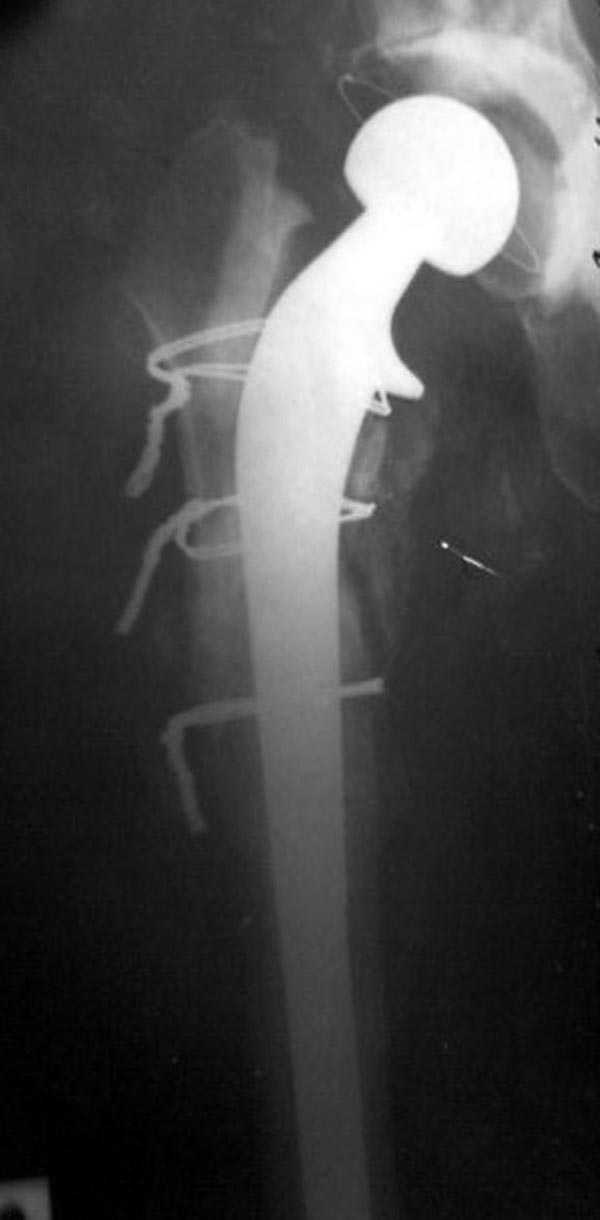

В дальнейшем заменил бы наружный фиксатор из частей аппарата Илизарова на более стабильный - стержневой фиксатор таз-бедро. В тазу можно применить полукольцо стержнями за крыло таза и дистально 2-3 стержня между передней и боковыми головками четерехглавой мышцы. Дельтовидная рама сверху вниз усилит конструкцию.

Следующий этап восстановление применением Blade Plate. Универсальный имплант и сегодня является уникальным по механическим характеристикам для восстановления проксимального отдела бедра где имеется сложная биомеханика.

Имеющиеся 130 градусные для вальгуса пластины от

Synthes короткие всего на две дырки, выход, обычная длинная 95 градусная Blade Plate разгибается до 105-110 градусов. Металл трудно поддается деформации, и его не согнуть между тепловой батереей в операционной, надо подготовить заранее после предварительного нагрева в механической мастерской.

Проведя клинок горизонтально в шейку, и соединив с

диафизом бедра создаем небольшой вальгус, тем самым увеличиваем длину конечности. Образовавшийся дефект кости надо заполнить блоком цемента, который предупреждает инфицирования и дает устойчивость конструкции. После затихания процесса можно приступить ко вторичному заполнению аутокостью или можно применить костную массу из того же местного костного регенерата.

Обещанный Synthesом локинг вариант пластины еще до нас не дошел, но блокирующая на пластине шайба поможет созданию локинг концепт.